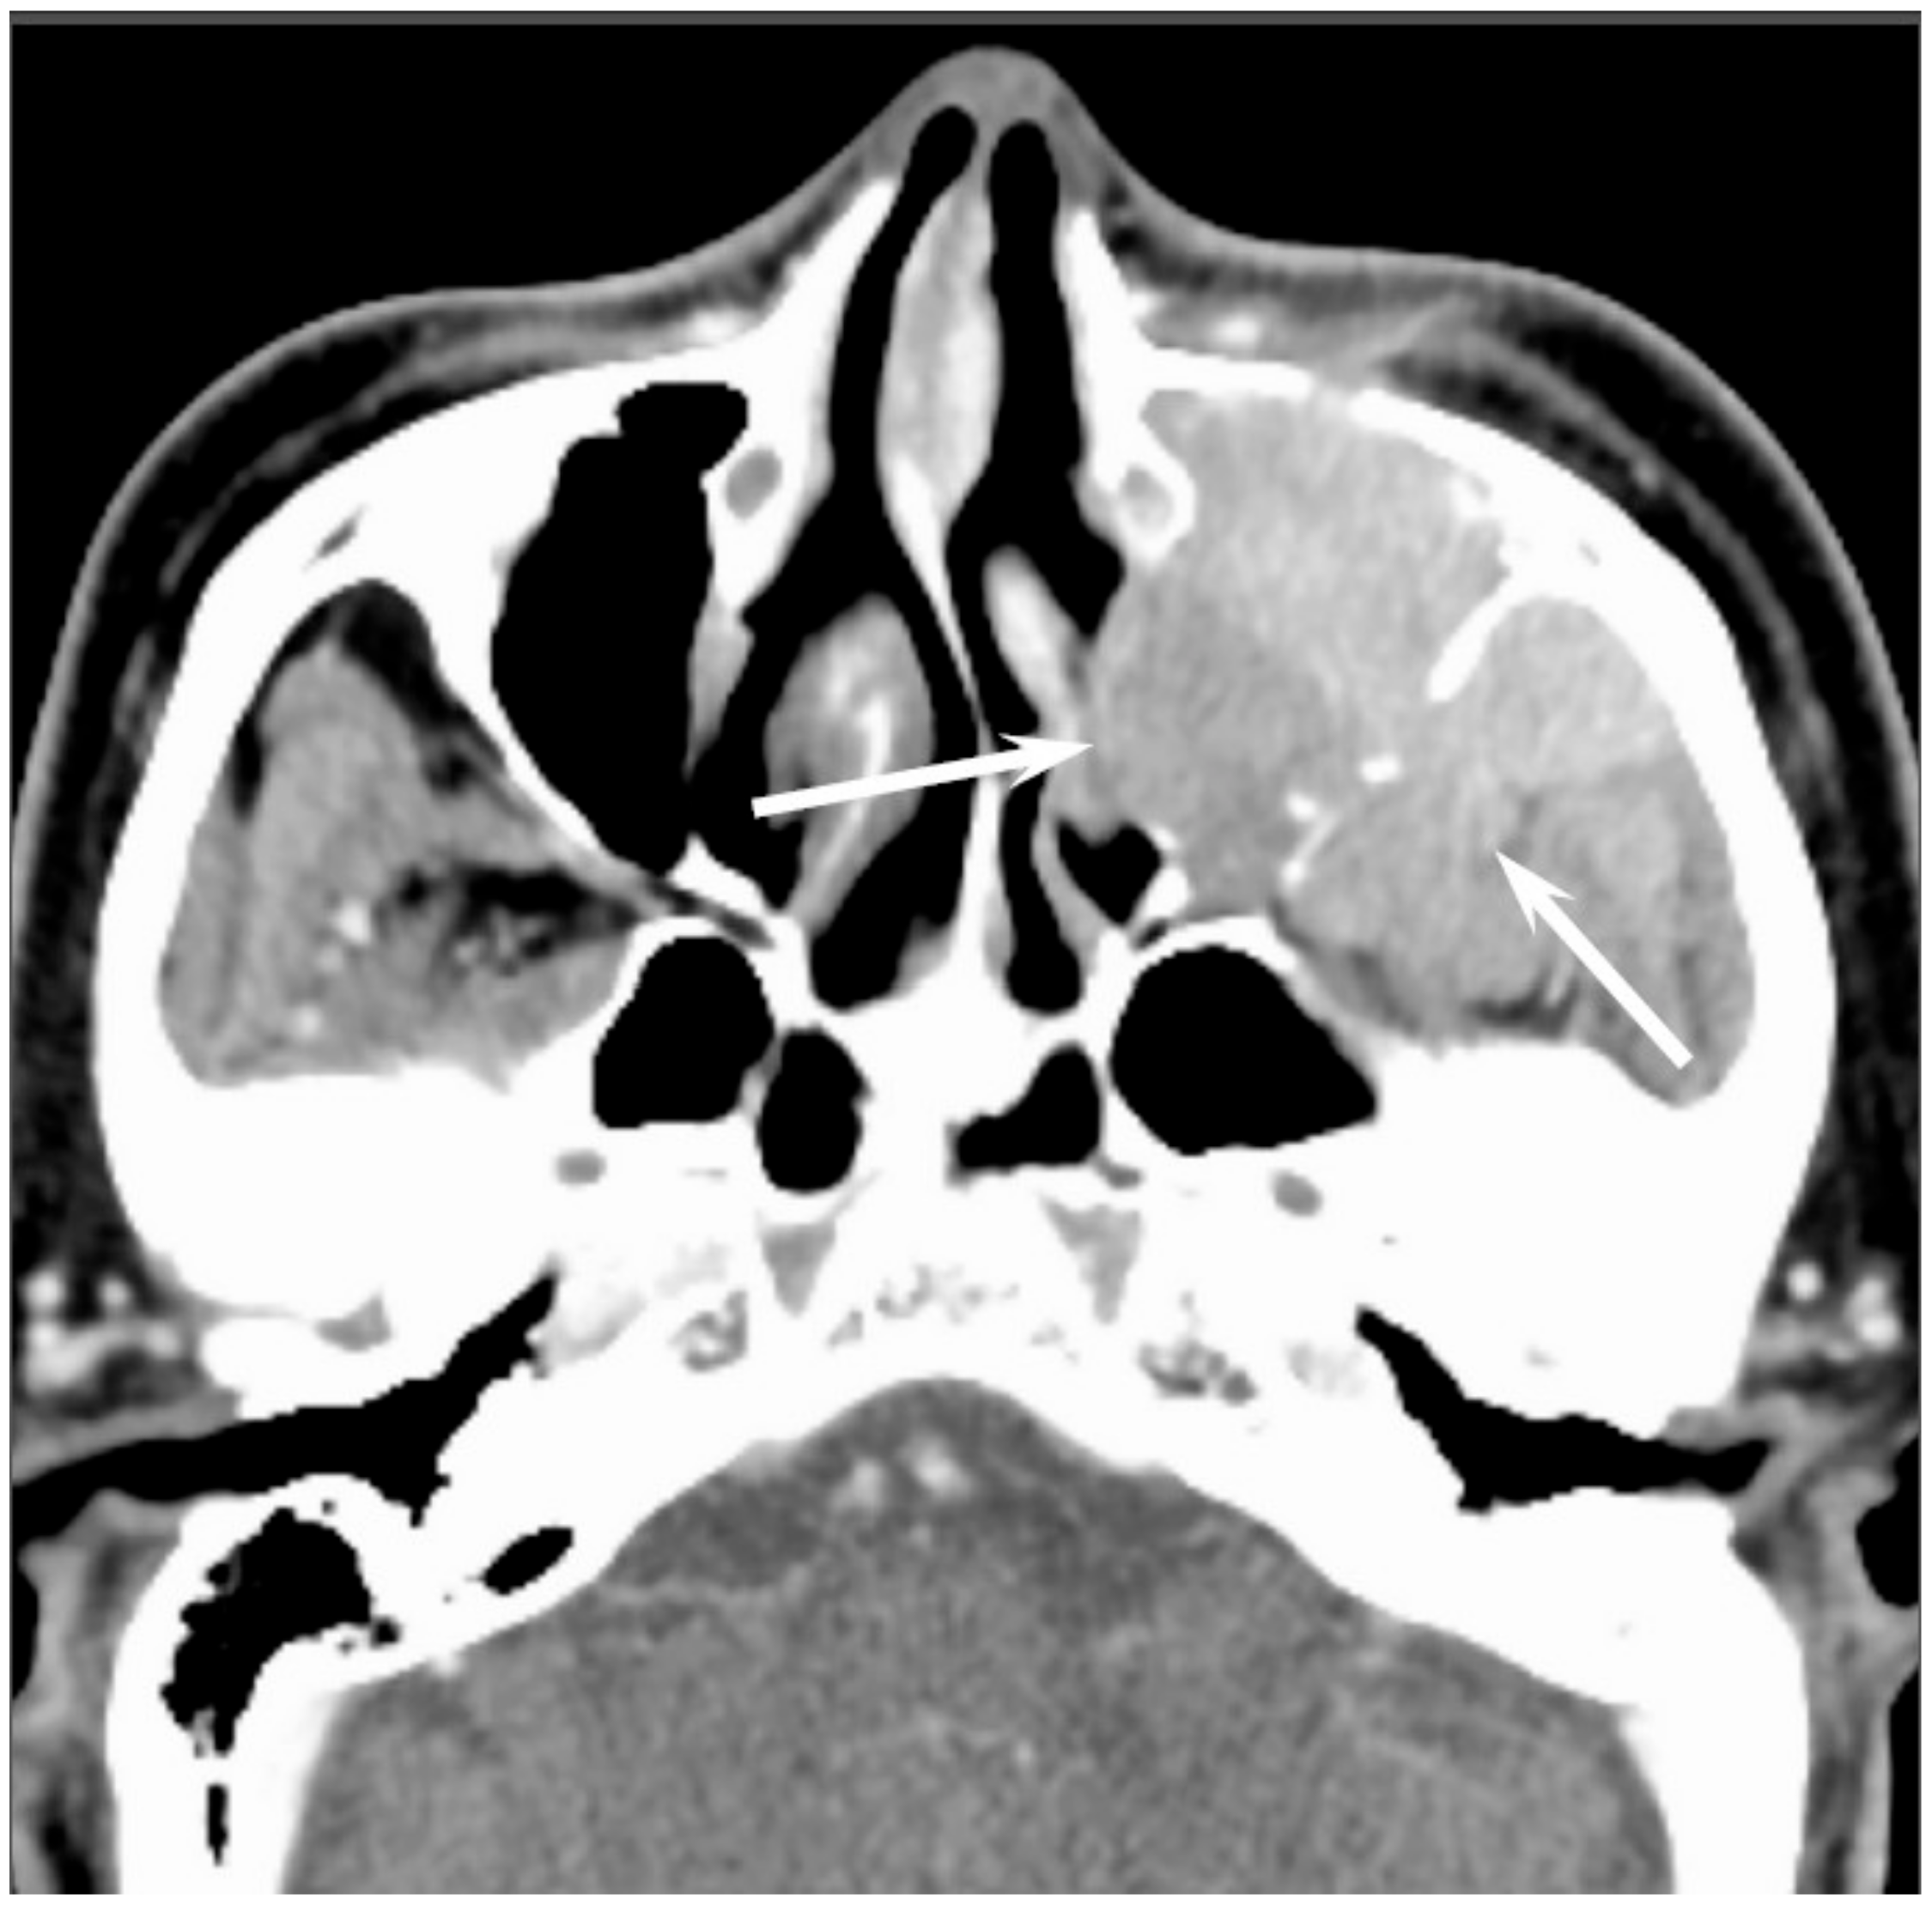

Sinonasal SCCs are characterized by aggressive bony destruction of the adjacent sinus walls (Figure 1). Because sinonasal SCCs are often detected at an advanced stage, the invasion of the contralateral sinonasal area, orbital wall, infratemporal fossa, and skull base is sometimes observed. Hypoxia is a common feature in most cases of SCC, and prolonged oxygen deprivation often leads to chronic hypoxic stress and consequent tumor necrosis [10]. Thus, intratumoral necrosis is also one of the characteristic findings in SCCs. On MRI, isointensity on T1WI, slight hyperintensity on T2WI, and moderate enhancement on contrast-enhanced T1WI are typical and nonspecific imaging findings for SCCs. Smaller lesions are typically homogeneous, whereas larger tumors are usually more heterogeneous and exhibit areas of necrosis and hemorrhage [11]. In the maxillary sinus, the ADC values of SCC (0.95 × 10−3 mm2/s) were higher than those of non-Hodgkin’s lymphoma (NHL) (0.61 × 10−3 mm2/s) [12].

Figure 1. Squamous cell carcinoma of the left maxillary sinus. Contrast-enhanced CT image showing an ill-demarcated, heterogeneously enhanced bulky mass with extensive bony destruction (arrows).